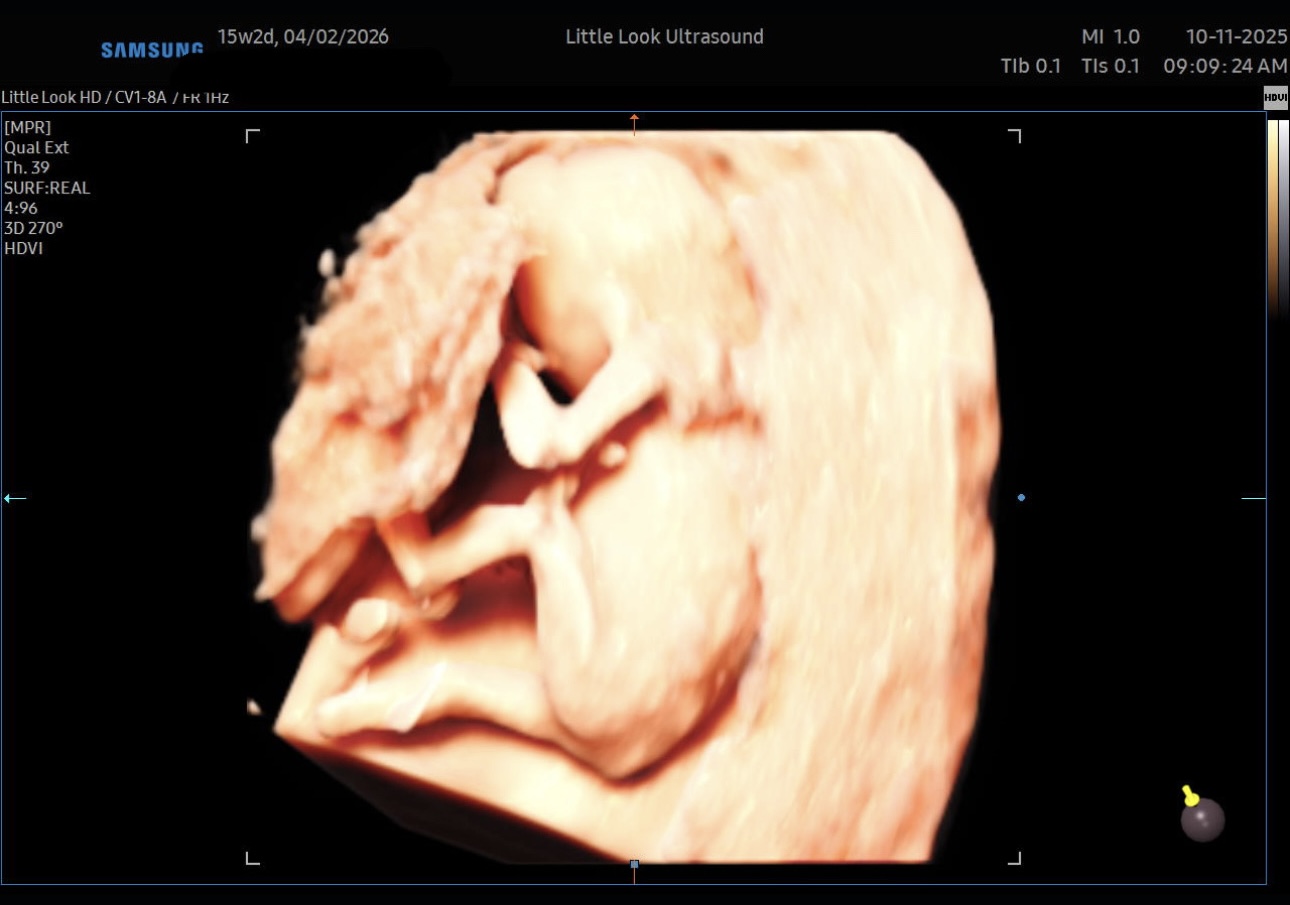

A Peek Inside: 3D/4D Ultrasound at 15 / 16 Weeks in Southern NH

Pregnancy is full of “firsts” — first heartbeat, first fluttering kicks, first trimester checkups. For many parents, one of the most magical moments is seeing baby in 3D or 4D ultrasound. If you’re around 15 weeks along and considering a 3D/4D scan (especially near southern New Hampshire / the MA border), here’s what you should know — from what’s possible to tips to get better images.

- A 3D ultrasound takes those same sound-wave echoes and reconstructs a volumetric (three-dimensional) image, giving more depth and a more “life‑like” picture of baby’s shape, contours, and features.

- A 4D ultrasound is essentially a 3D image in motion — i.e. video in real time, showing baby moving, yawning, stretching, etc.

These “bonding” ultrasounds are often offered as elective (non-diagnostic) services, like at our private imaging center Little Look Ultrasound in Southern NH!

- Facial features are still rudimentary. You might see the outline of a nose, lips, cheeks.

- Because baby is still small and skin is thin, not much fat is developed.

What You Might See at 15/16 Weeks

Here are some of the features many parents report (and that clinics advertise) being visible at ~15 weeks:

| Head, body, limbs | Quite likely — you may see baby’s full form (tiny arms, legs, torso) if position is good. |

| Hands, fingers, toes | You might catch baby opening fingers, curling toes, stretching. |

| Some facial outline | Possible: nose, mouth, cheeks, if baby faces toward the probe and isn’t obstructed. |

| Movement / motion | Yes — baby may wiggle, yawn, stretch, wave limbs; these are fun to watch in 4D. |